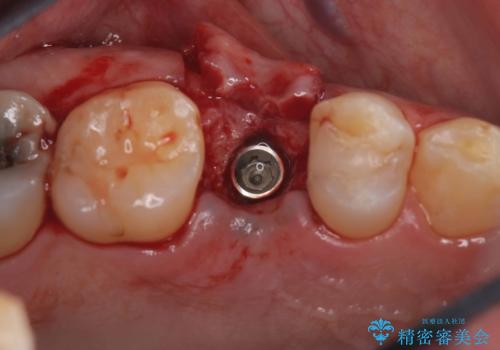

右上5番が根尖性歯周炎と歯周病が同時に併発しており、骨が大きく溶け、歯の動揺も著しかったため保存困難と判断をし抜歯してインプラントで治療を行いました。

インプラントはインプラント周囲炎になりにくいスクリュータイプを使用しています。

従来のインプラント治療では、オペを二回に分けることが主流でしたが今は1回のオペで治療を終える事が出来るようになりました。

インプラントと骨が強度にくっつくように骨密度を上げながらドリリングを行っているのと、患者様の骨の状態に合わせてインプラントの形態を選ぶことで可能となっています。